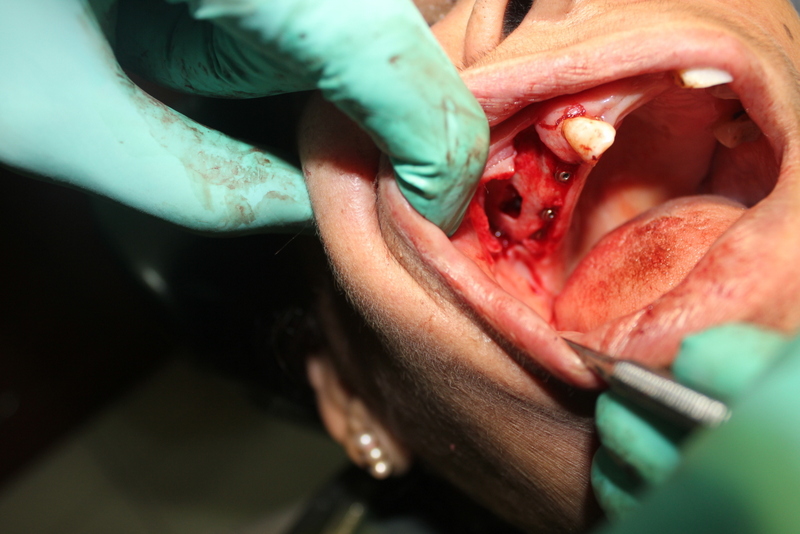

Apicoectomy